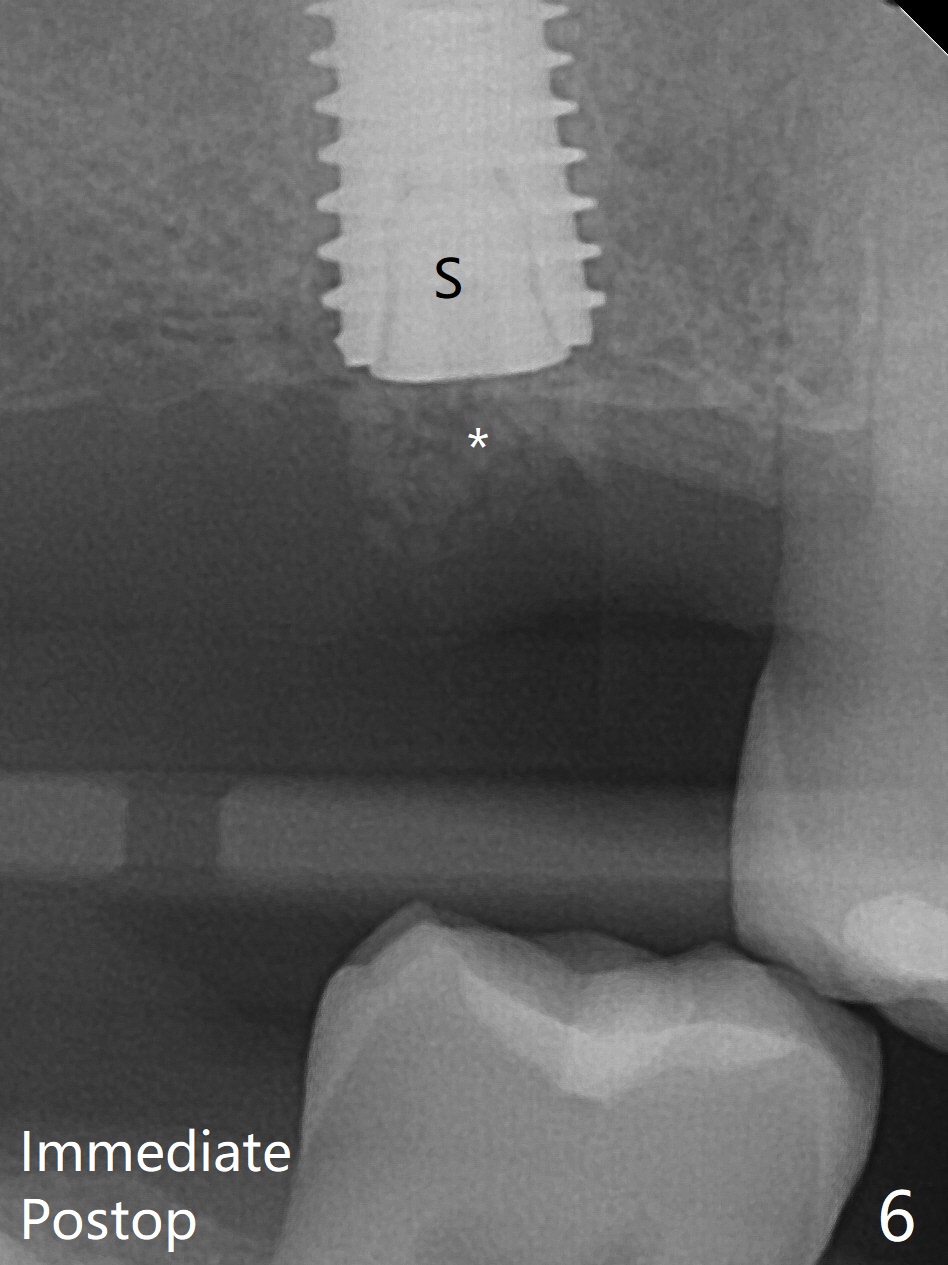

尽管事先准备15号刀片,看到完整2号牙牙槽嵴就舍不得切开。放置以前导板(用于即种),用软组织环形刀做个记号,接着用活检环形刀切取钻洞表面软组织,保存于PRF液体中。术前CT显示3号牙上方粘液囊肿(图一:*),而2号牙上方窦膜薄,总之两者都不好惹(容易感染,窦膜破),提升需要特别小心。完成初步钻洞后,使用17-19毫米长的DIO圆钻,放置粘性骨粉,使用4.5x10毫米报废植体进行提升(到第一横线),结果窦底没有穿(图二:红箭头)。接着使用尖头钻头从原来2.2x5.3毫米一直到3.5x10毫米,几乎每使用一个钻头后都检查窦底完整性,再放置骨粉,使用4.0x10毫米植体提升(到第二横线),好像穿过窦底(图三)。再加骨粉,使用4.5x10毫米植体扭力底,最后放置PRF膜,很难塞入上颌窦,结果只能从钻洞上端近中很小裂口塞入,植入5x8.5毫米正式植体(图四),上颌窦里骨粉呈蘑菇状(*)。临床检查腭侧(P)植体牙槽嵴下,其余骨壁难于判断。而咬翼片却显示植体颊侧(B),腭侧均在牙槽嵴下(图五)。为了减少术后骨质吸收,放置愈合螺帽后(图六:S),植体表面添加骨粉(*),最终把保存的软组织放回原位(二期手术:减少上颌窦与口腔交通,感染),牙周胶水粘固(图七)。术后没有鼻出血。